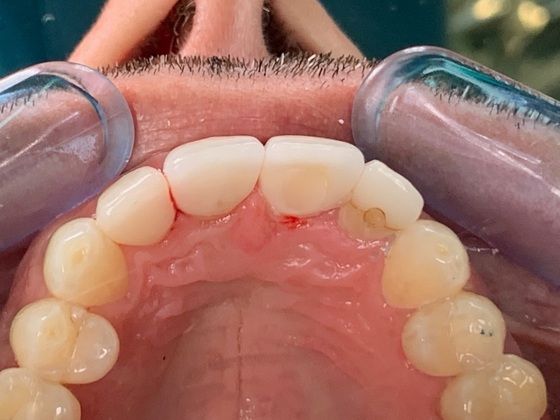

Internal or external resorption of roots is an idiopathic condition affecting teeth in traumatic occlusion. It is a "silent killer" of teeth. We recently completed a case where one tooth had to be replaced with a dental implant and the other required a new dental crown following the exploration of its root for evidence of internal resorption. The Nobel Biocare implant system was used and the patient never went without a tooth. Immediate temporization during the surgery to remove the root was deployed and the patient was not inconvenienced by a removable temporary solution.